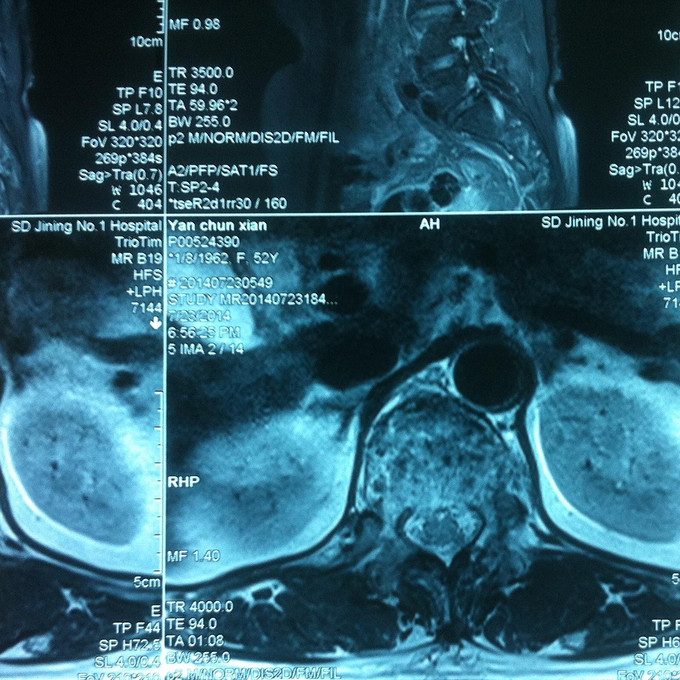

查体:腰部叩痛,腰部活动受限,双下肢感觉无异常,双侧屈髋、伸膝、踝背伸、踇背伸、跖屈肌肌力4-5级,双侧膝腱反射++,跟腱反射+,双侧巴氏征阴性, 影像学检查MR:腰椎骨折,累及中柱。

诊断:腰椎骨折 处理:1、完善相关辅助检查,明确诊断,有无手术指证; 2、患者拒绝行腰椎后路撑开复位内固定术;3、给予绝对卧床,在床上行腰部逐渐加软垫复位,配合促骨愈合、消肿药物。